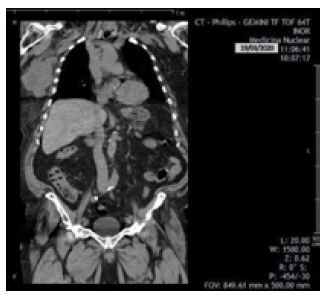

Ultrasound showed that the left breast had no alterations, but the right breast had a fatty breast pattern, an extensive solid nodular area located in the upper outer quadrant and axillary extension, microlobulated margins associated with skin thickening (6mm), and signs of lymphedema of the subcutaneous cellular tissue. This examination established that the right breast lesion was classified as BI-RADS 5; in addition, the right axilla showed lymph nodes classified as BRN-4 according to Rostagno's classification, which corresponds to lymph nodes >3.5mm in size with increased thickness and/or focal thickening of the cortex (Figure 1).

Patient's breast ultrasound.

Figure 1: Patient's breast ultrasound.

Source: Image obtained while conducting the study.